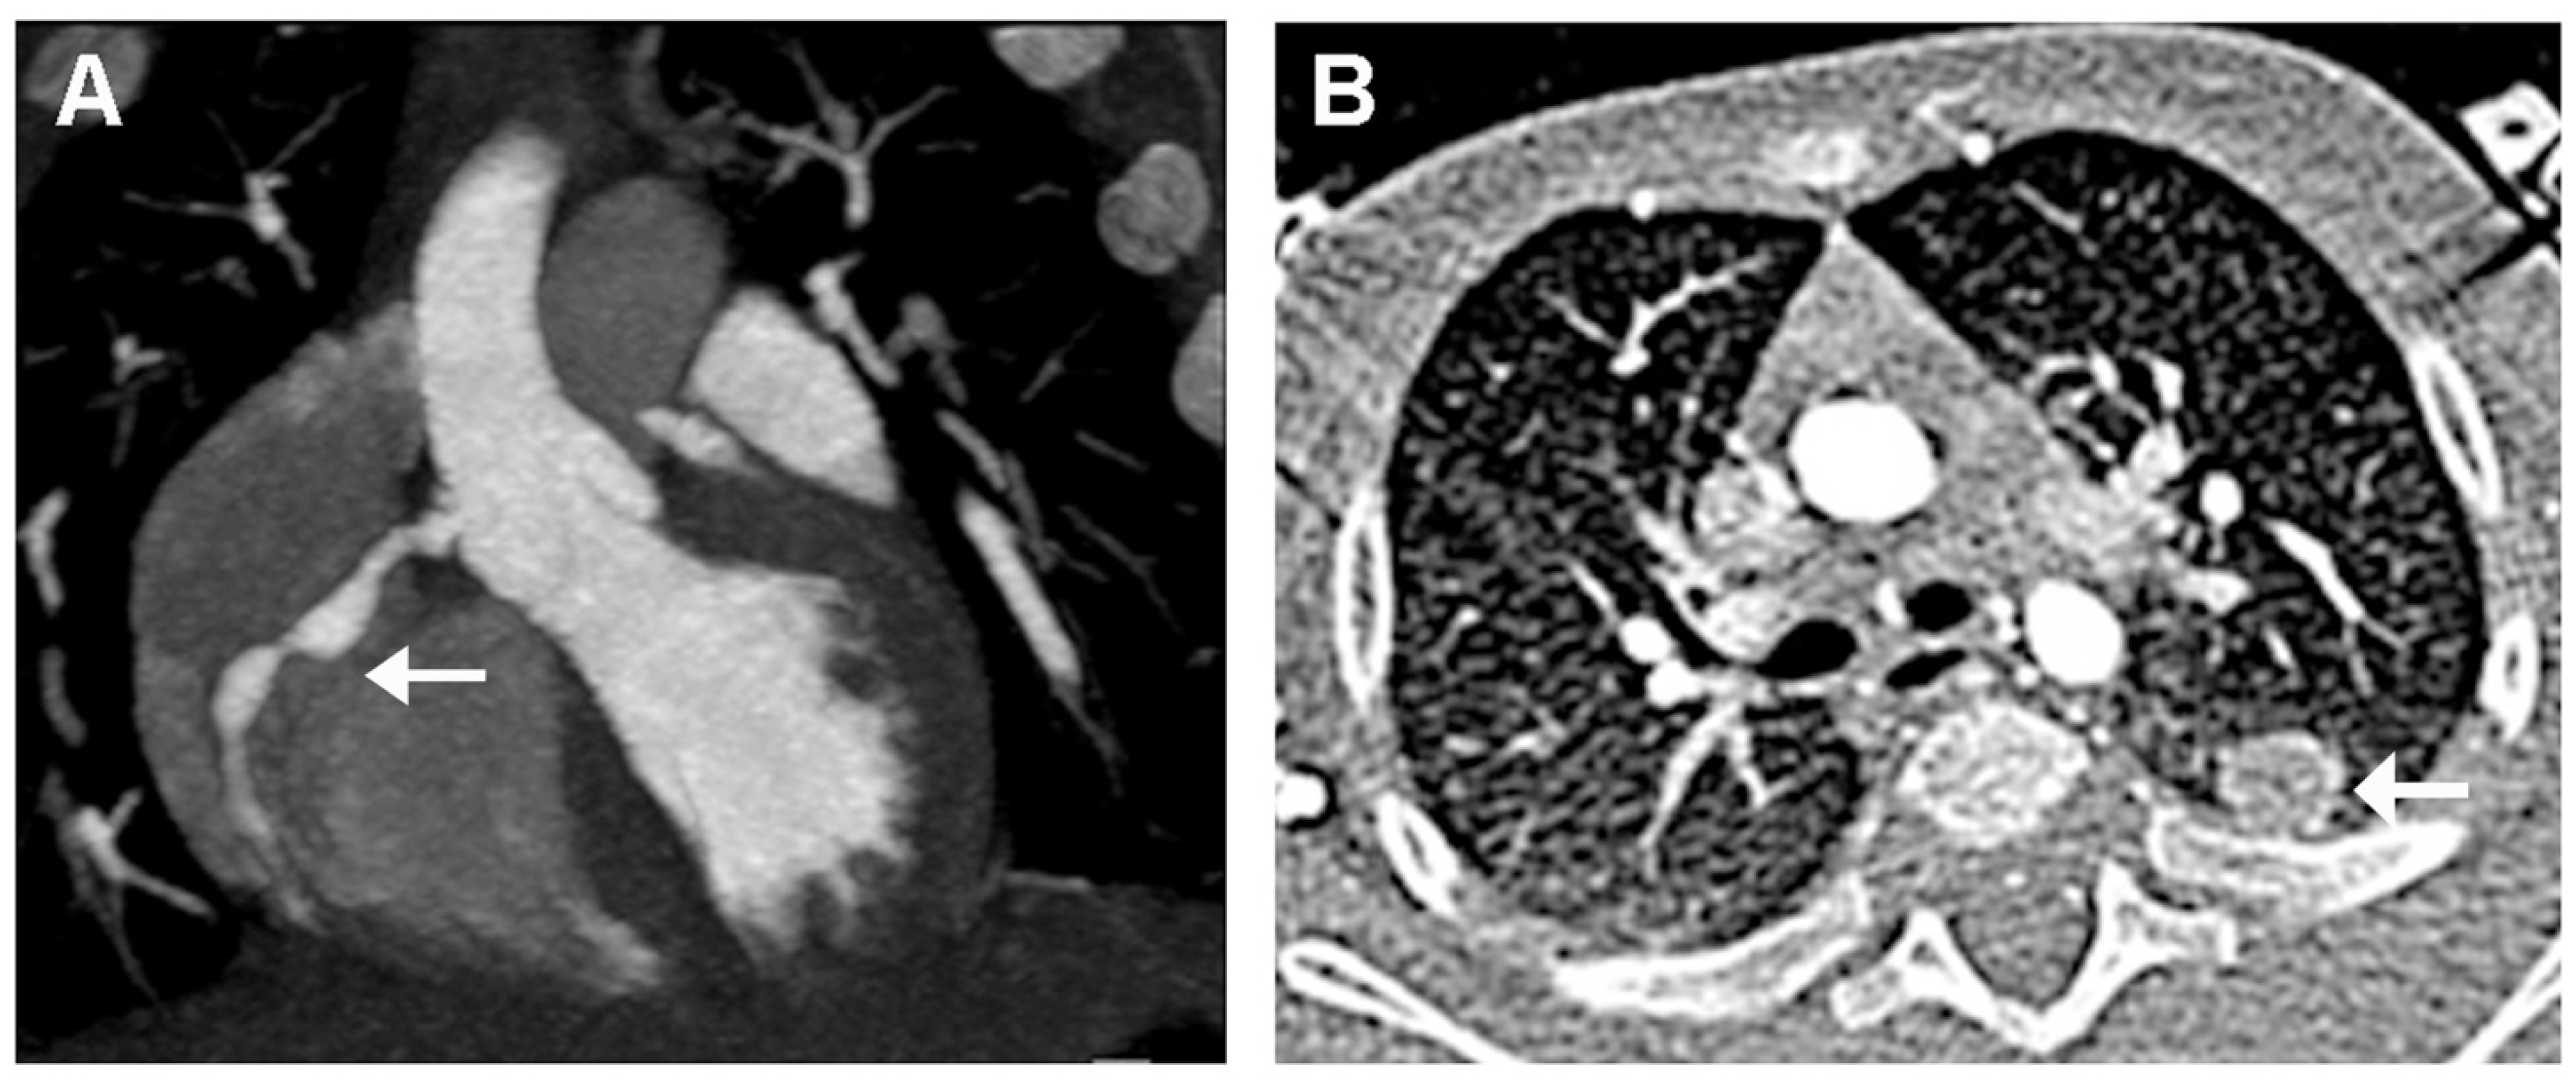

2. Case Presentation